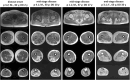

Recent research has sparked a discussion on the spectrum of diseases linked to the MATR3 gene associated with amyotrophic lateral sclerosis and distal myopathy with vocal cord and pharyngeal weakness (VCPDM). To date, fewer than 50 cases of VCPDM have been reported in the literature. We aim to build upon the work of previous researchers by gathering additional information about VCPDM. In this study, we present six patients from four unrelated families affected by VCPDM. Our observations include patients exhibiting both the typical phenotype associated with MATR3-related distal myopathy and rare symptomatic manifestations of the disease. Notably, two cases presented with an asymmetric scapuloperoneal phenotype, leading in one case to an initial misdiagnosis of facioscapulohumeral muscular dystrophy.